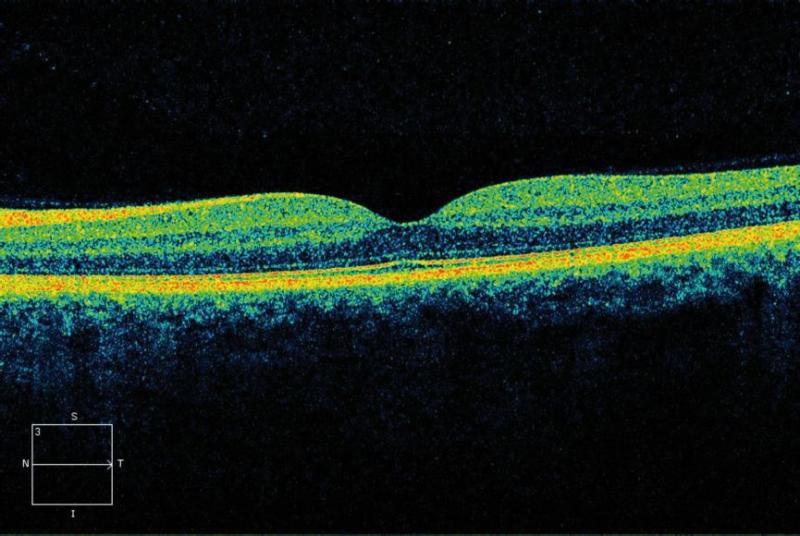

Eye care professionals often use OCT to examine the back of the eye, to check specific areas such as the retina and macula. This helps them diagnose and monitor retinal and macular eye conditions, such as diabetic retinopathy and macular degeneration. As the macula is responsible for central vision, seeing fine details, and colour vision, OCT images can pick up changes that directly affect a person’s vision. For example, OCT technology can detect if there is any swelling in the macula that may lead to blurred or distorted vision.

An OCT scan showing a healthy macula and its various layers.